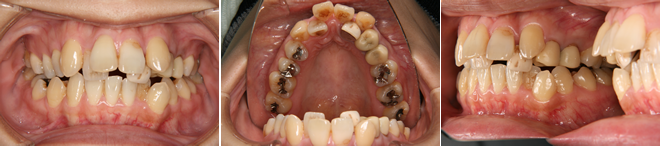

| 主訴 | 前歯が出ている |

| 年齢・性別 | 35歳 / 女性 |

| 治療方針 | 叢生も前歯の突出も大きいケース。小臼歯抜歯だけでは改善できないため、大臼歯の抜歯も行なった。 |

| 抜歯部位 | 上下顎左右小臼歯、左上第1大臼歯(計5本) |

| 使用装置 | マルチブラケット装置 |

| 治療期間 | 36か月 |

| リテーナー | 上顎インビジブル、フィックス、下顎インビジブル |

| 費用 | 885,000円(税別) |